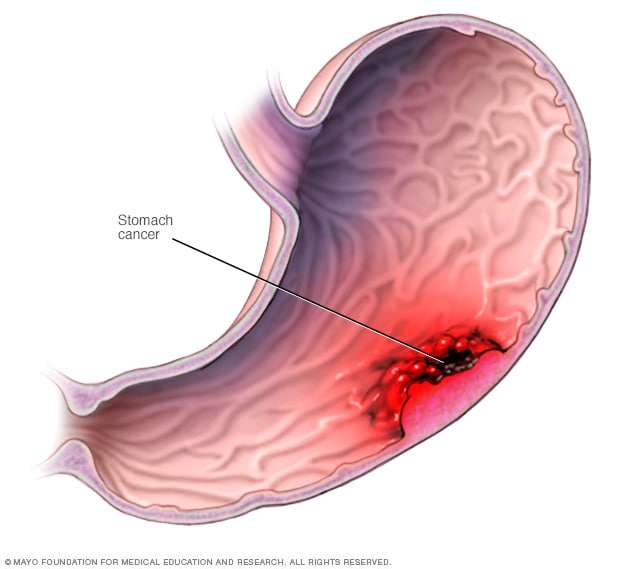

images of stomach cancer

Stomach Cancer – Causes, Symptoms, Diagnosis and Treatment

Stomach cancer – Mayo Clinic